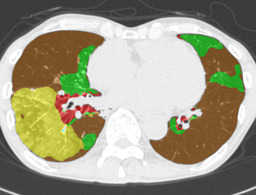

In this paper, we define partial annotation as an annotation format in which only one class is chosen for the annotation and only pixels belonging to the chosen class are annotated per image. For example, in Figure 1(a), although there is ground glass opacity in the image, only consolidation is chosen for annotation and pixels of consolidation are annotated. Partially annotated dataset is less informative for training, however, it is much easier to create compared to fully annotated dataset since annotators only need to focus on one class at a time during the annotation task.

Partially annotated datasets have been utilized previously [8, 9]. In this paper, we propose a new weak supervision technique that fully utilizes partially annotated dataset. Throughout this paper, each DLD pattern is represented or painted in the following colors (CON:cyan, GGO:yellow, HCM:red, EMP:green, NOR:brown.)

Statistics of our dataset are shown in Table 1 and typical images and their annotations for each DLD pattern are shown in Figure 1. In our partially annotated dataset, all the pixels in a slice were manually classified into two classes: dominating DLD pattern and other tissues. In other words, all the pixels in our dataset were assigned one of the labels from either of the two label sets, Lstrong={lCON,lGGO,lHCM,lEMP,lNOR}subscript𝐿𝑠𝑡𝑟𝑜𝑛𝑔subscript𝑙𝐶𝑂𝑁subscript𝑙𝐺𝐺𝑂subscript𝑙𝐻𝐶𝑀subscript𝑙𝐸𝑀𝑃subscript𝑙𝑁𝑂𝑅L_{strong}=\{l_{CON},l_{GGO},l_{HCM},l_{EMP},l_{NOR}\} or Lweak={lCON¯,lGGO¯,lHCM¯,lEMP¯,lNOR¯}subscript𝐿𝑤𝑒𝑎𝑘subscript𝑙¯𝐶𝑂𝑁subscript𝑙¯𝐺𝐺𝑂subscript𝑙¯𝐻𝐶𝑀subscript𝑙¯𝐸𝑀𝑃subscript𝑙¯𝑁𝑂𝑅L_{weak}=\{l_{\overline{CON}},l_{\overline{GGO}},l_{\overline{HCM}},l_{\overline{EMP}},l_{\overline{NOR}}\}. For example, in Figure 1(a), colored pixels were labeled as lCONsubscript𝑙𝐶𝑂𝑁l_{CON} and all the other pixels were labeled as lCON¯subscript𝑙¯𝐶𝑂𝑁l_{\overline{CON}}. In this paper, we call pixels of label lLweak𝑙subscript𝐿𝑤𝑒𝑎𝑘l\in L_{weak} and lLstrong𝑙subscript𝐿𝑠𝑡𝑟𝑜𝑛𝑔l\in L_{strong} as weakly annotated pixels and strongly annotated pixels respectively. Our pixel-wise annotations were created in the following steps. First, up to 3 slices were chosen for the annotation for each HRCT scan and for each slice, one representing DLD pattern was chosen by a radiologist. Second, three radiologists performed pixel-wise binary annotation (e.g. binary annotation between lCONsubscript𝑙𝐶𝑂𝑁l_{CON} or lCON¯subscript𝑙¯𝐶𝑂𝑁l_{\overline{CON}}) for each slice. Finally, the radiologists’ annotations were merged by taking majority classes for each pixel (i.e. pixels labeled as a DLD pattern by more than 2 radiologists became the corresponding DLD pixel). In addition to the DLDs annotation, lung fields were manually segmented under the supervision of radiologists and training and testing were conducted only within the lung fields.

Figure 1: Typical slices for each DLD classes. Slices of HRCT are shown in lung window setting (window-center=-600, window-width=1500) with annotated labels superimposed in transparent colors. Note that even if more than one DLD patterns existed, only one DLD pattern was chosen and annotated for a slice to facilitate the annotation process.